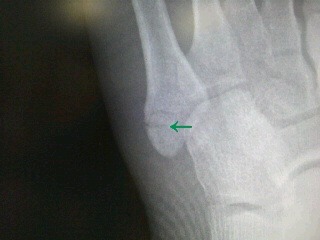

医師が教える手や足の骨折を早く治す方法